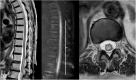

Background: Vascular lesions of the spinal cord are rare but potentially devastating conditions whose accurate recognition critically determines the clinical outcome. Several conditions lead to myelopathy due to either arterial ischemia, venous congestion or bleeding within the cord. The clinical presentation varies, according with the different aetiology and mechanism of damage.

Purpose: The aim is to provide a comprehensive review on the radiological features of the most common vascular myelopathies, passing through the knowledge of the vascular spinal anatomy and the clinical aspects of the different aetiologies, which is crucial to promptly address the diagnosis and the radiological assessment.